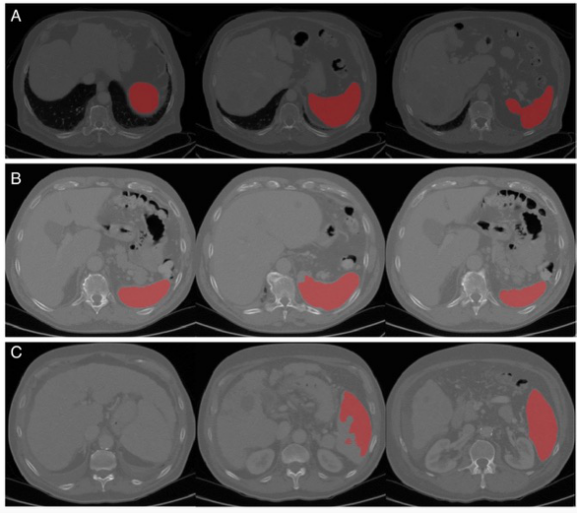

圖 算法性能的代表性圖像(從左到右是脾臟上部、中部和下部的圖像)。A完美的分割,B可接受的分割(中間有輕微的分割錯誤),C差的分割(上部有主要的分割錯誤,有吻合的肝臟和脾臟現象)